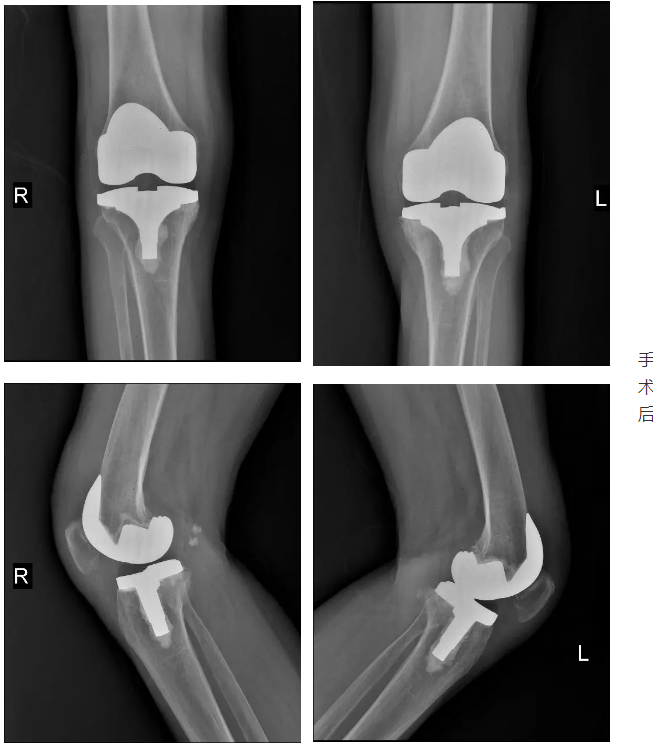

偶然听病友说:西安凤城医院骨科好,还有专门的骨关节专业。就抱着试试看的态度来到我院。经雷永林主任仔细询问病史,详细查体并拍片检查、测量,诊断:双膝关节骨性关节炎。因患者病史时间较长,各种治疗方法都用过了,效果不佳,关节畸形严重,需行人工膝关节置换手术治疗。入院后经积极术前准备,第3天雷永林主任团队为患者一次行双侧人工膝关节置换术。术后麻醉清醒坐起后患者看到双腿伸直了,说这下没有“罗圈腿”了。术后第2天取除引流管后,医生就让下床活动。老太太下床活动后看着腿直直的,走路也好看了,高兴的向医生护士直竖大拇指。

患者女儿说道:现在术后6个月了,走路不疼了,腿也直了,连个子都高了,整个人精神、年轻、自信多了。终于能和她们老姐妹们一起外出旅游,享受祖国的大好河山了。看着老太太这样,父亲和我们兄妹也放心多了。真的非常感谢西安凤城医院骨科一病区,治疗关节病真的很专业。